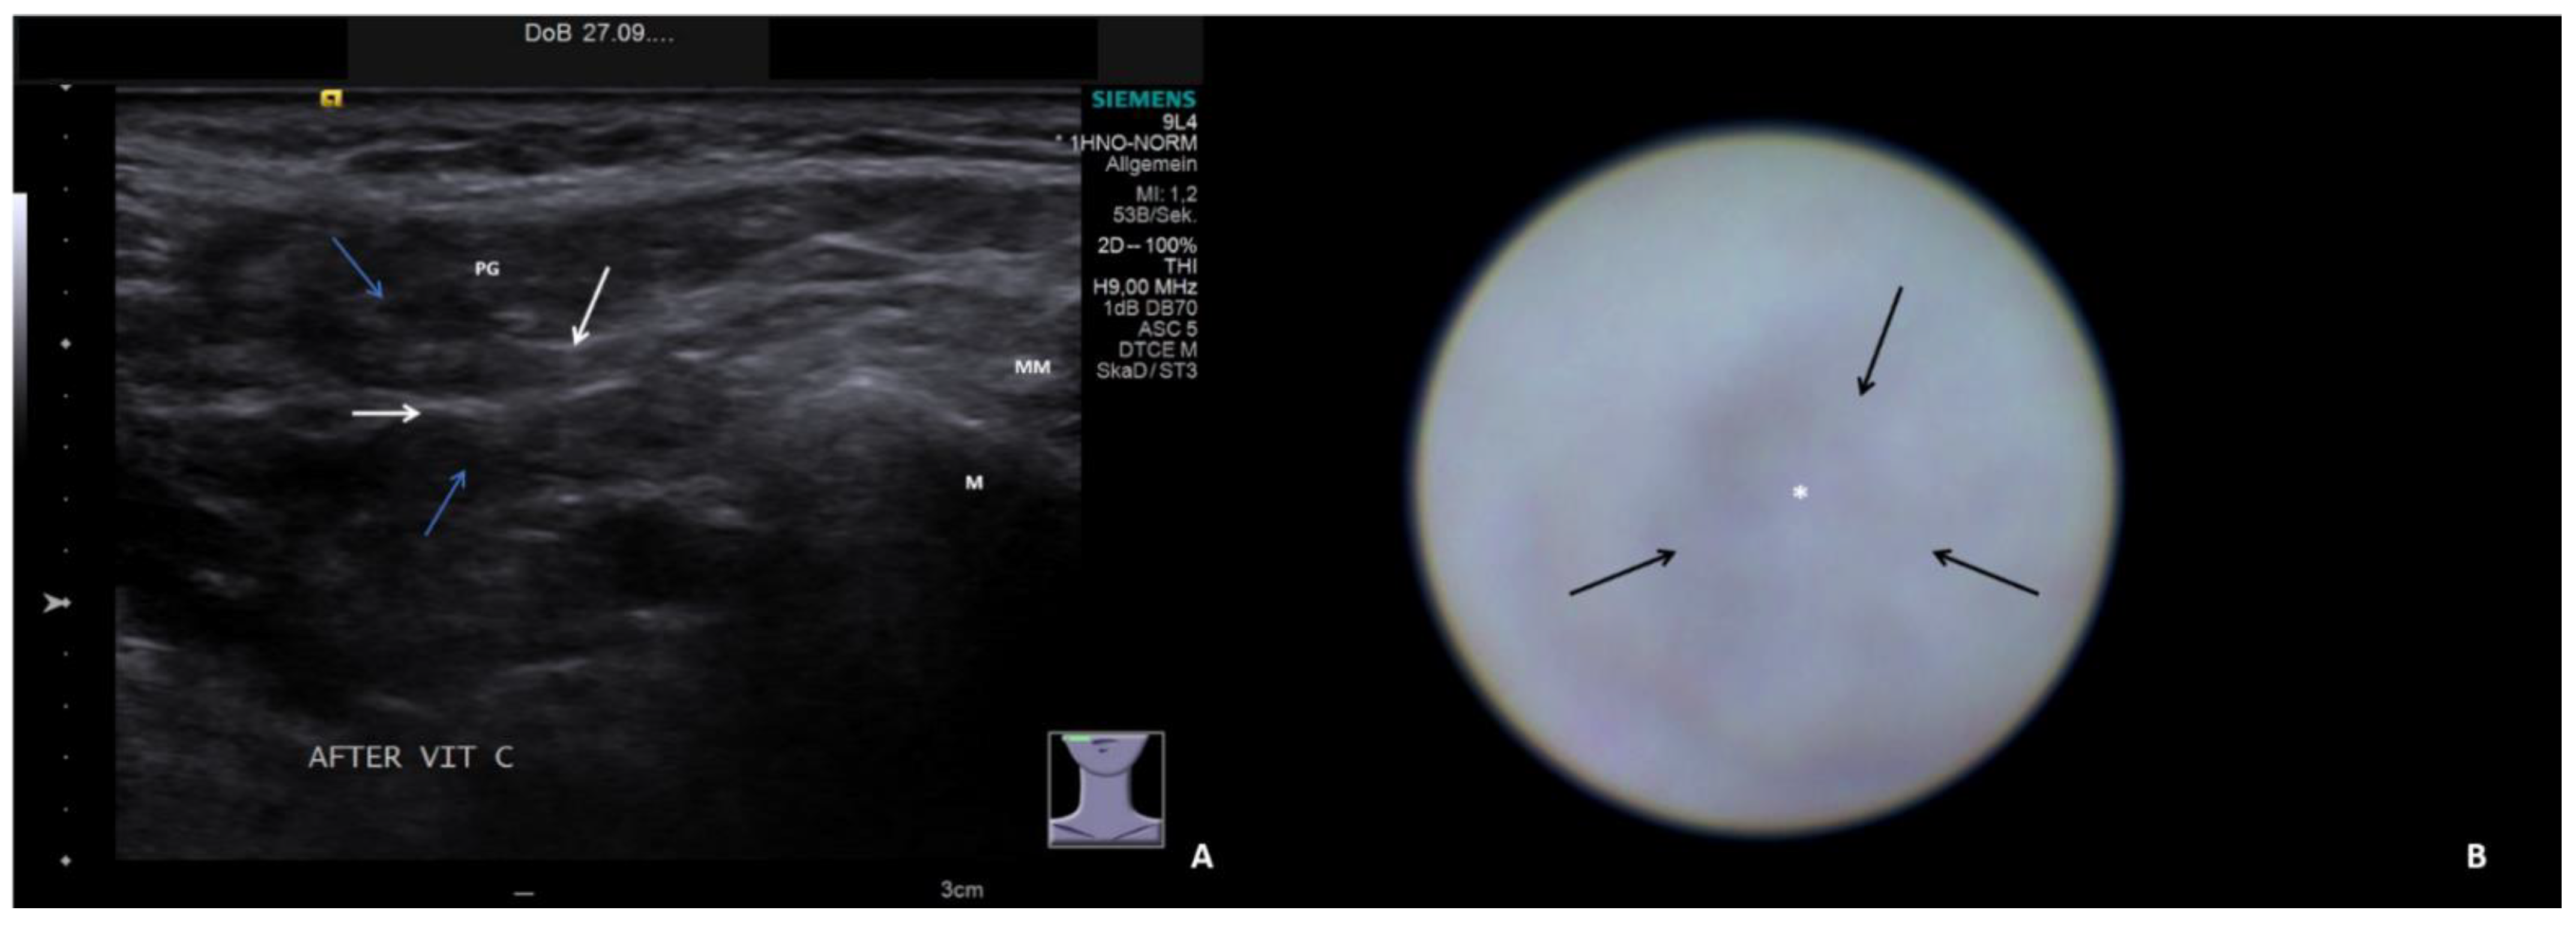

- Hypoechoic and homogeneous (no relevant loss of gland parenchyma; Figure 1A)

- Chronic sialodochitis (SD: inflammation, paleness of the duct wall, plaques, discharge; Figure 1B; Supplementary Video S1)